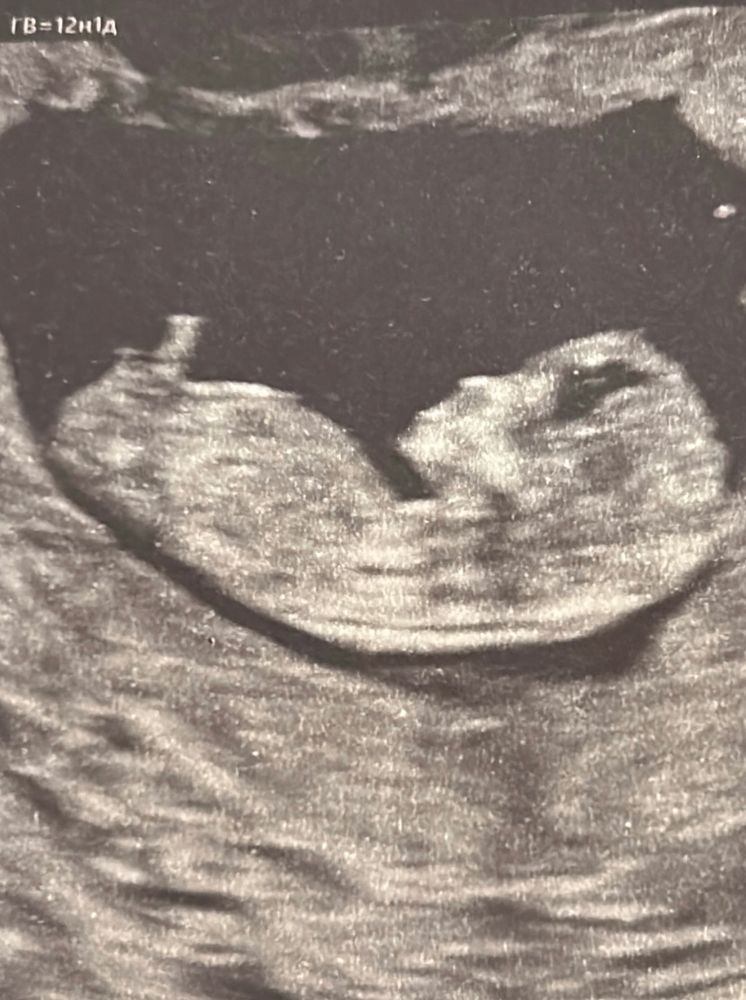

1 скрининг, пол

Пол малышаДобрый вечер дамы, предлагаю увлекательное занятие - погадать на кофейной гуще и поглазеть на малышка)

onetwo , у девочек задрана вверх, у мальчиков либо четко прямо либо клюет вниз, мне узист объясняла. Тут задрана вверх

Гроза Райсполкома, вообще-то наоборот 😄это у парней вверх задрано) а у девочек бугорок параллельно позвоночнику идет

Чудесная барышня))). Тк вертикальное «ответвление» уж очень похоже на пуповину (искривлено и одного диаметра).

Марфушенька-душенька, не, на него не смотрю. Скорее всего это нога вообще попала либо пуповина да. Барышня есть на страничке у меня ниже, там прям видно хорошо было, что девочка 😅 а тут как-то не вижу такую пипку горизонтальную